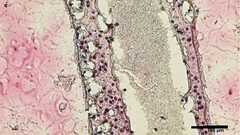

Des scientifiques de l'Université de Colombie-Britannique (UBC) ont réussi à imprimer en 3D des répliques de structures tubulaires productrices de sperme à partir de cellules testiculaires viables. Le matériel de bio-impression a été collecté par biopsie de cellules souches testiculaires de patients atteints d'azoospermie non obstructive (ANO), la forme la plus lourde d'infertilité masculine. Ces protocellules ont ensuite été cultivées et multipliées avant d'être imprimées en 3D dans une structure tubulaire similaire à celle des spermatozoïdes situés dans les testicules humains

Non seulement la méthode de bio-impression a été couronnée de succès en termes de survie des cellules, mais après 12 jours, les tubes ont été examinés et le matériau "avait mûri en plusieurs cellules spécialisées impliquées dans la production de sperme". De plus, les faux tubes testiculaires "montraient une amélioration significative du maintien des cellules souches spermatogoniales - deux signes précurseurs des capacités de production de sperme", indique le rapport. Selon le chercheur principal de l'étude, le Dr Ryan Flannigan, professeur adjoint d'urologie à l'Université de Colombie-Britannique :

L'objectif de l'équipe de recherche est maintenant d'expérimenter l'alimentation des cellules bioprintées avec divers nutriments et facteurs de croissance appropriés afin de les inciter à produire des spermatozoïdes viables qui pourraient ensuite être utilisés dans de nouveaux traitements de l'infertilité pour les couples qui essaient de concevoir.